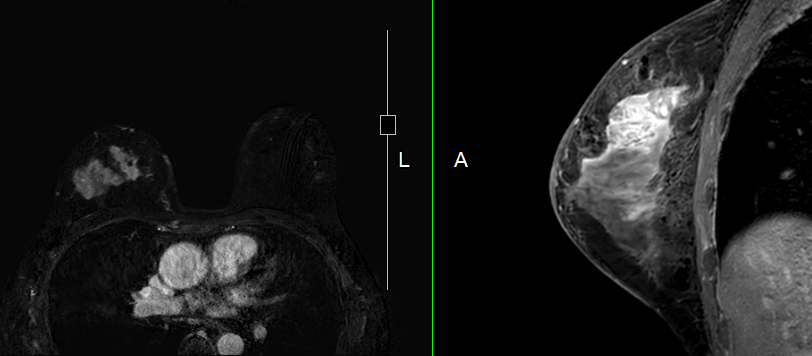

乳房MRIの最新技術と応用に関する詳細な情報を提供する専門書。- タイトル: Breast MRI: State of the Art and Future Directions- 巻号: Volume 5- 編集者: Kaya P. Pincus, Ritesh Mann, Savannah Partridge- 出版社: Academic Press- 内容: 乳房MRIの最新技術と応用に関する情報- キーフィーチャー: 乳房MRIの技術、解釈、最新の研究成果に関する情報ご覧いただきありがとうございます。